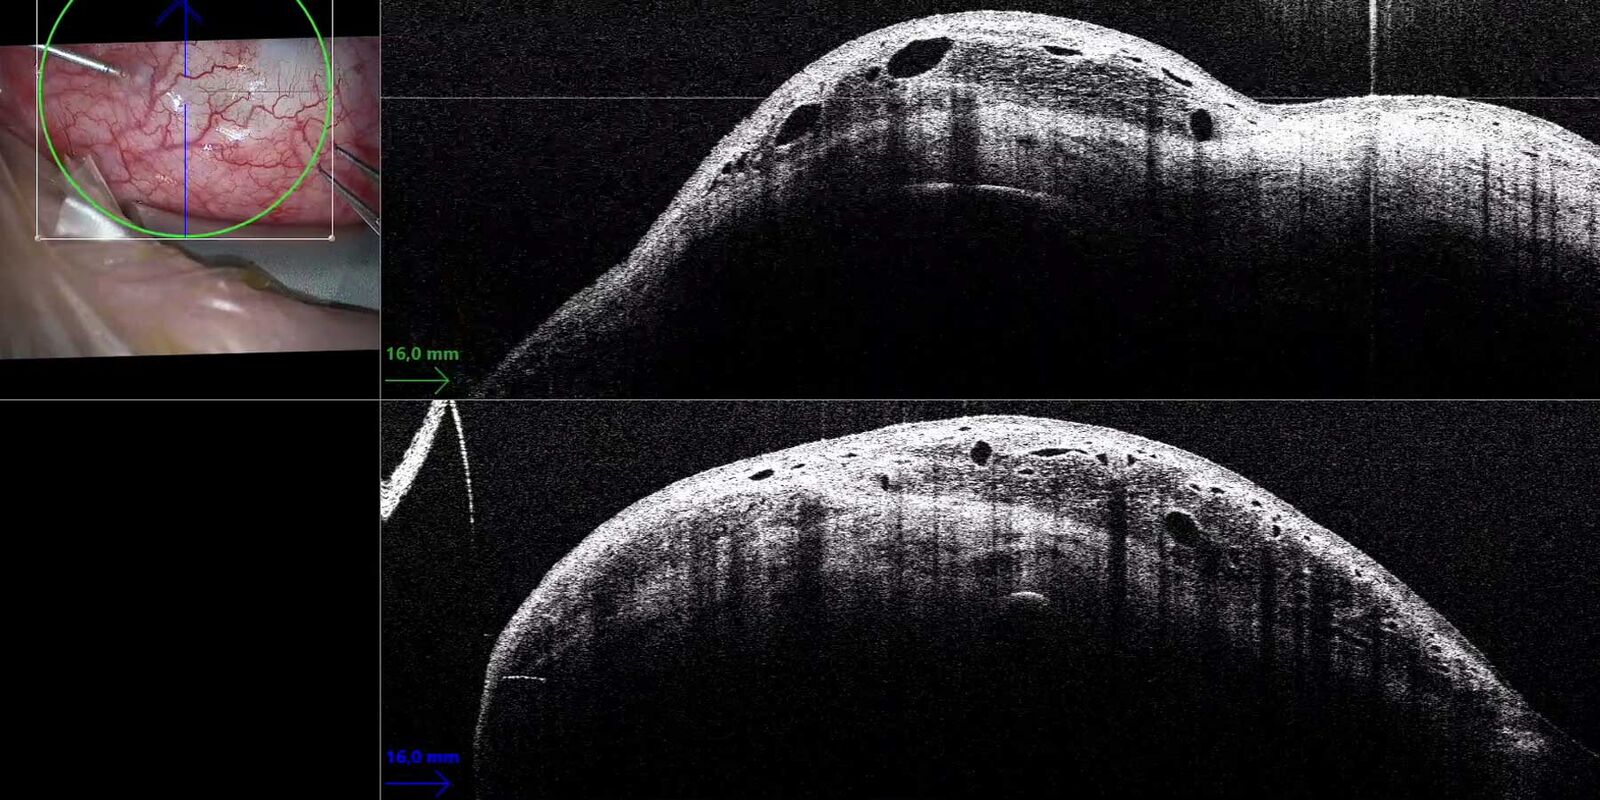

PVR u 4 latkiwsparcie śród operacyjnego OCT Leica Enfocus Proveo 8 Leica Enfocus The optimized enfocus design lets you work in a more comfortable and relaxed posture at the microscope. Enfocus is an intrasurgical oct upgrade solution for new and existing surgical microscopes. See the details you are looking for with high. I need assistance/training in how to. Enfocus oct medical equipment pdf manual download. The enfocus intraoperative oct system built into the. Leica Enfocus.